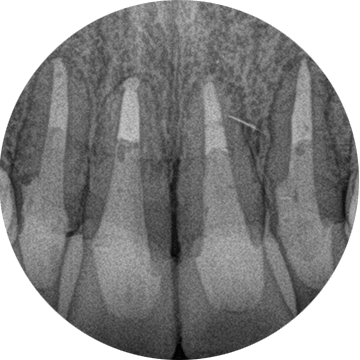

症例5【50代男性】前歯4本の根尖病巣

治療前

治療後(24ヶ月後)